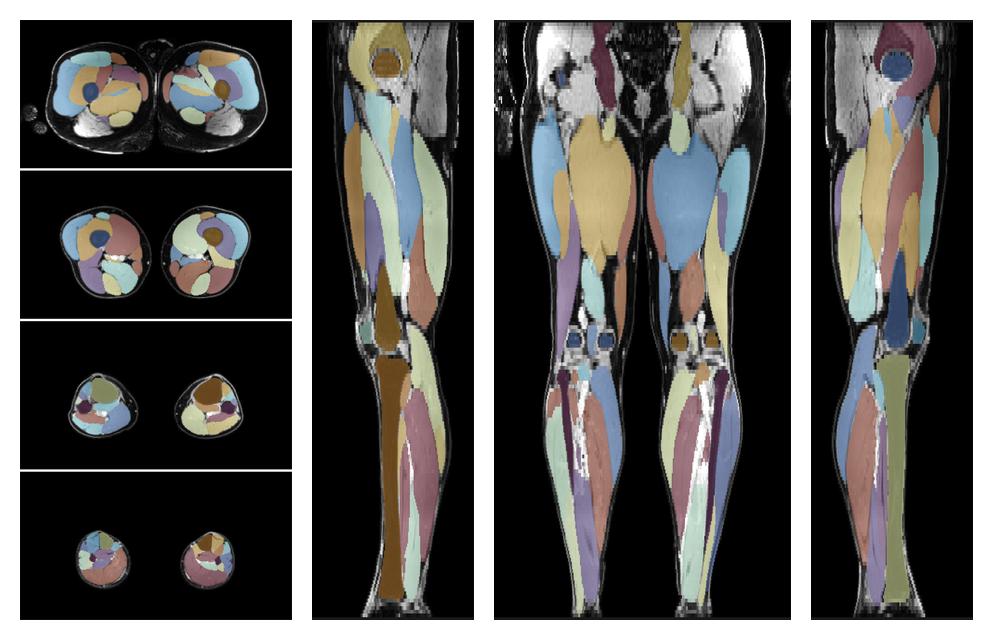

Muscle segmentation

Convolution neural network based (UNET) fiber automated muscle segmentation, for information look here».

• Automated muscle and bone segmentation.

Overlay of automated muscle segmentation labels on dixon water image.